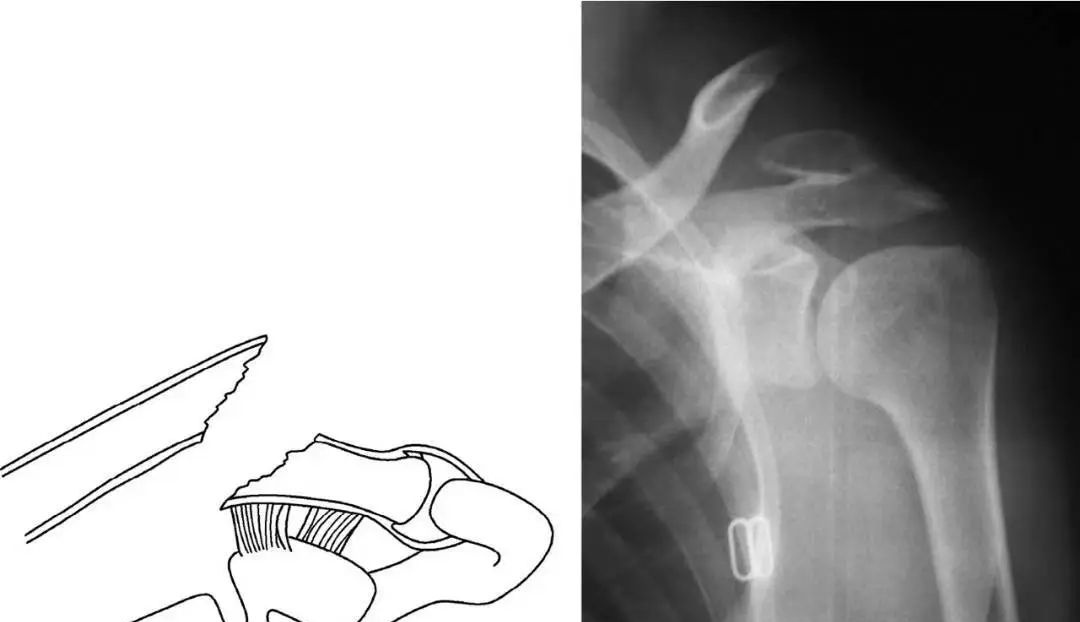

因此,我们目前所采取的方法为应用缝合锚钉(SuperRevo Anchor)加异体肌腱进行固定。手术采取60°沙滩椅位,经肩峰后角向喙突做Langer切口,切开三角肌~胸大肌筋膜显露骨折后对骨折进行复位,对断裂的喙锁韧带清创而不进行修补,以两枚缝合锚打入喙突基底,锁骨上钻孔后将缝合锚的尾线依次穿过骨孔后打结固定,为加强固定效果,加用异体肌腱绕过喙突基底并穿过锁骨孔后打结固定。术后颈腕吊带制动3周后开始肩关节功能锻炼。

锁骨板有哪些【每周科普】锁骨骨折分中段、外段、内段,治疗方式也有差异_https://www.jmylbn.com_新闻资讯_第14张

我们用此方法治疗了近百例患者,目前未发现出现固定失效的情况,术后随访结果显示肩关节功能大多获得了良好的恢复。